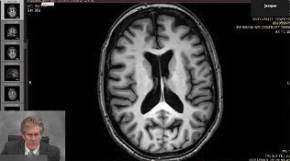

Proving a Traumatic Brain Injury

Use of DTI to Prove TBI

mTBI Tutorial

JAMA Study mTBI April, 2022.